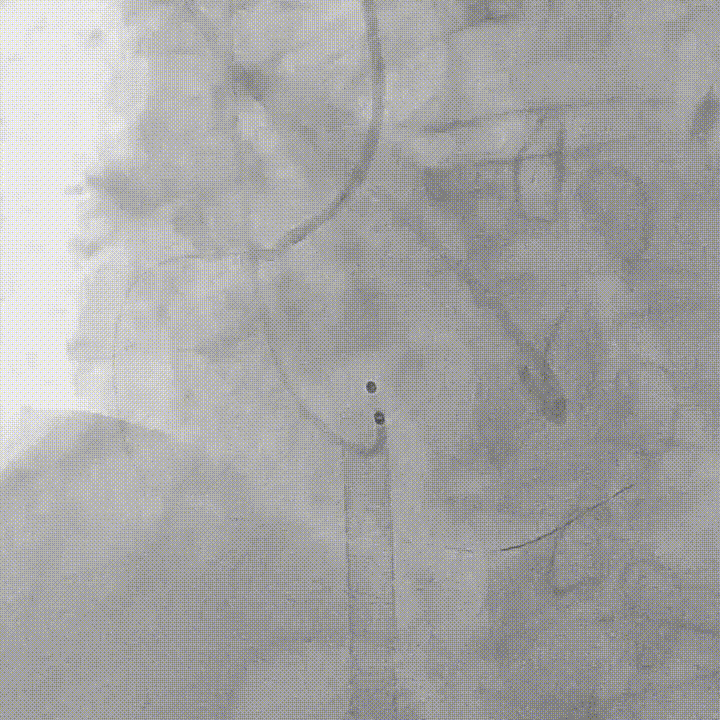

术前行右冠造影,发现存在多段管腔狭窄,血流受限,初步行球囊扩张以改善灌注,同时评估支架植入可能性;

右冠造影及球囊扩张

在保护右冠的前提下,精确释放开窗支架,恢复右冠灌注,随后行球囊后扩确保瓣膜贴壁充分,兼顾瓣膜功能与冠脉通畅;

右冠保护下球囊后扩

复查造影及食道超声示瓣膜位置,形态满意,瓣周漏较前明显好转,右冠血流恢复,无栓塞迹象;

术后造影